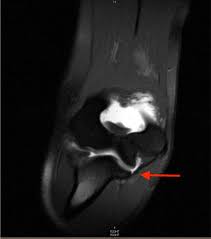

This can lead to pain, a sense of instability or looseness, and an inability to work or play sports. The ulnar collateral ligament (ucl) acts as the primary static restraint to the resultant valgus force upon the elbow, and the estimated force upon the ligament with pitching approaches the known limit of the ligament's tensile strength. The ligaments are stretched, but not torn. Medial collateral ligament (mcl) injuries are graded into three groups on mri, much in the same way as many other ligaments:. Patients who sustain an ulnar collateral ligament (ucl) tear will experience elbow pain, numbness, and swelling.

Injury patterns of the ulnar collateral ligament in a cadaveric model in progress. A ligament serves as a tether between the bones. Ulnar collateral ligament (ucl) injuries continue to be a major source of morbidity in baseball players. Subsequently requiring primary repair of the collateral ligament which resulted in good outcomes. Medial ulnar collateral ligament injury, or a tommy john injury, is characterized by attenuation or rupture of the ulnar collateral ligament of the elbow leading valgus instability in overhead throwing athletes; A grade 3 sprain indicates a complete tear of the ligament is present. Medial collateral ligament (mcl) injuries are graded into three groups on mri, much in the same way as many other ligaments:. As a result, injuries to the ulnar collateral ligament in the professional baseball pitcher are quite common. The ulnar collateral ligament (ucl) acts as the primary static restraint to the resultant valgus force upon the elbow, and the estimated force upon the ligament with pitching approaches the known limit of the ligament's tensile strength. Grade 1 and 2 injuries are treated by splinting. Symptoms of an acute ligament sprain will be sudden onset pain on the inside of the elbow. An ulnar collateral ligamenttear or sprain could occur with valgus overload or stress movement from pitching or throwing. The incidence of injury continues to rise at …